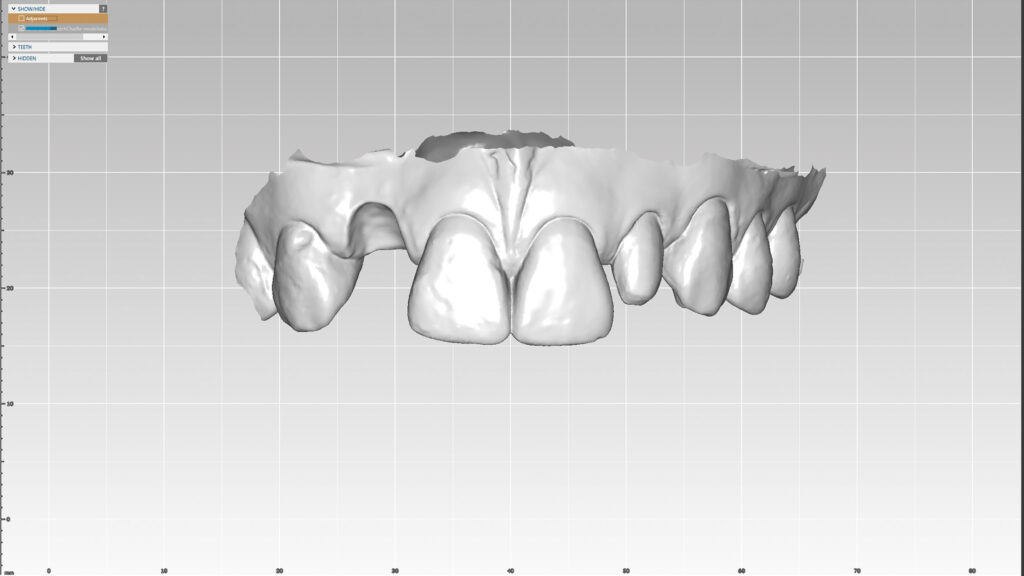

Einer der Vorteile bei der Arbeit mit dem Intraoralscanner ist, dass die digitale Erfassung bei maximaler Okklusion erfolgen kann. Zudem kann die STL-Datei direkt an das Labor übermittelt werden. Die Konstruktion des virtuellen Modells erfolgt mit der Software DTX Studio Design. Anschließend werden die STL-Dateien exportiert und mit einem 3D-Drucker physische Modelle hergestellt (Abb. 5). Um die gescannte Okklusion wiederherstellen zu können, werden die STL-Dateien von Ober- und Unterkiefer getrennt gedruckt. Auf dem Modell wird der Milchzahn regio 12 „extrahiert“ und der periimplantäre Gingivaverlauf ideal gestaltet (Abb. 6 und 7). Höhe und Form des gegenüberliegenden seitlichen Schneidezahns dienen als Vorlage.

Digitales Set-up (DTX Studio)

Nachdem Zahn 12 auf dem gedruckten Modell entfernt worden ist, kann das Modell mit dem Laborscanner (KaVo LS3) digitalisiert und ein Design-Setup am Bildschirm konstruiert werden (Abb. 8). Die Software-Bibliothek bietet eine breite Auswahl an Zähne in verschiedenen Formen sowie Größen und erlaubt eine Zahnaufstellung in optimaler Position (Abb. 9 und 10). Diese Vorgehensweise spart Zeit und ermöglicht noch mehr ästhetische Kreativität. Der KaVo LS3-Desktop-Scanner ist für die Planung von Implantatversorgungen mit DTX Studio verbunden. DTX Studio ist eine digitale Plattform, die Diagnose und Behandlung verbindet und die Kommunikation im Behandlungsteam optimiert.